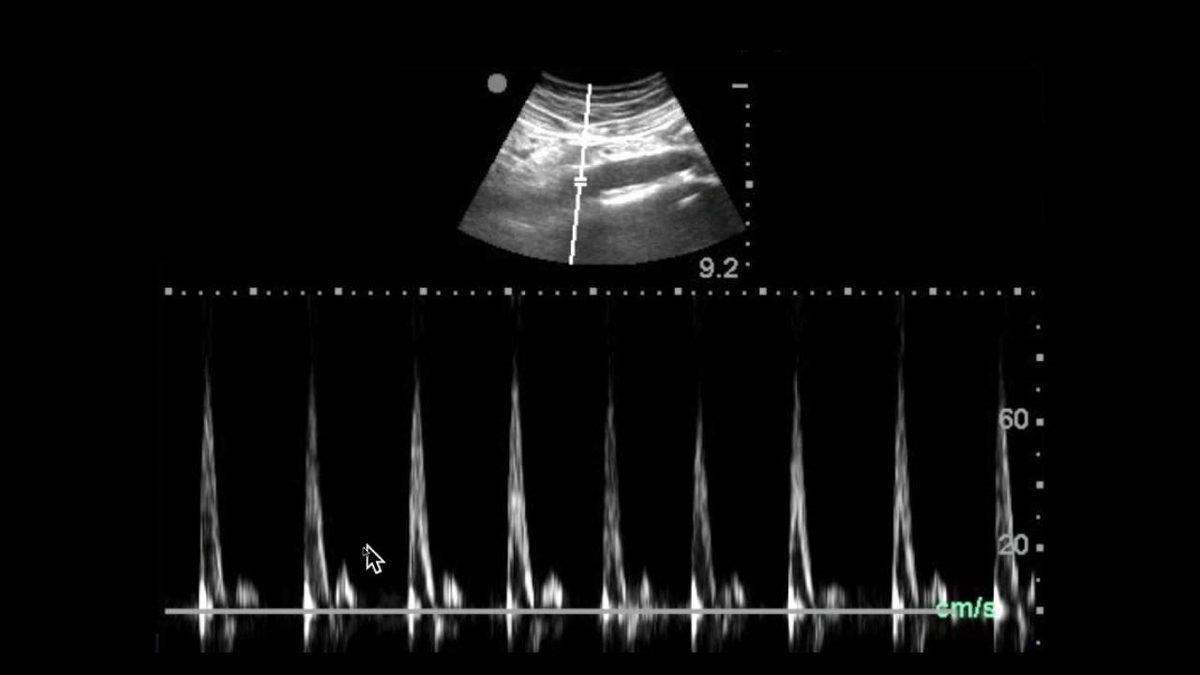

2 boyutlu ultrason:

2 boyutlu ya da diğer adıyla obsetrik ultrason, gebe kadınlarda standart kontroller sırasında kullanılan bir ultrason türüdür. Hamileliğin herhangi bir döneminde yaptırılabilen 2 boyutlu görüntü elde edilen bu yönteme genel olarak 16. haftadan sonra başlanır. 2 boyutlu ultrason ile genel duruma bakılır, bebeğin kalbi dinlenir hatta cinsiyet tespiti bile yapılabilir.